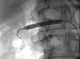

Balloon angioplasty complication

Angioplasty, also known as balloon angioplasty and percutaneous transluminal angioplasty (PTA), is a minimally invasive endovascular procedure used to widen narrowed or obstructed arteries or veins, typically to treat arterial atherosclerosis. A deflated balloon attached to a catheter (a balloon catheter) is passed over a guide-wire into the narrowed vessel and then inflated to a fixed size. [Source: Wikipedia ]